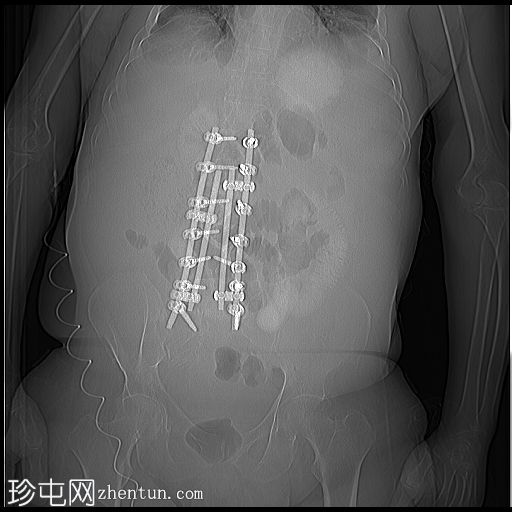

CT

定位扫描

图像

该老年男性患者,两个月前曾接受脊柱手术,并多次服用抗生素,现因急性腹痛和腹胀就诊。CT检查结果提示结肠炎,在此临床情况下最可能是假膜性结肠炎。